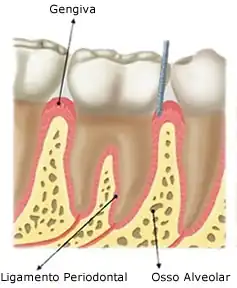

A arcada alveolar é a porção da maxila e da mandíbula que forma e suporta os alvéolos dentários. É formado quando o dente erupciona para promover inserção óssea para o ligamento periodontal em formação; quando o dente é perdido, desaparece gradualmente.

A arcada alveolar é contido de osso alveolar que reveste os alvéolos. Ele é composto de uma fina lâmina de osso cortical, com numerosas perfurações, que permitem a passagem de vasos sanguíneos entre os espaços medulares do osso e ligamento periodontal. A margem coronal do osso alveolar forma a crista alveolar, que geralmente está paralela à junção cemento-esmalte em uma distância de 1-2 mm para apical. O processo alveolar é o maior responsável pelo crescimento vertical da maxila, onde a maior deposição óssea ocorre no seu bordo inferior.

- Alojar as raízes dos dentes e mantê-los no arco.

- Absorver e distribuir as pressões oclusais geradas durante os contatos dentários;

- Ancorar os dentes aos alvéolos através da inserção das 'fibras de Sharpey'